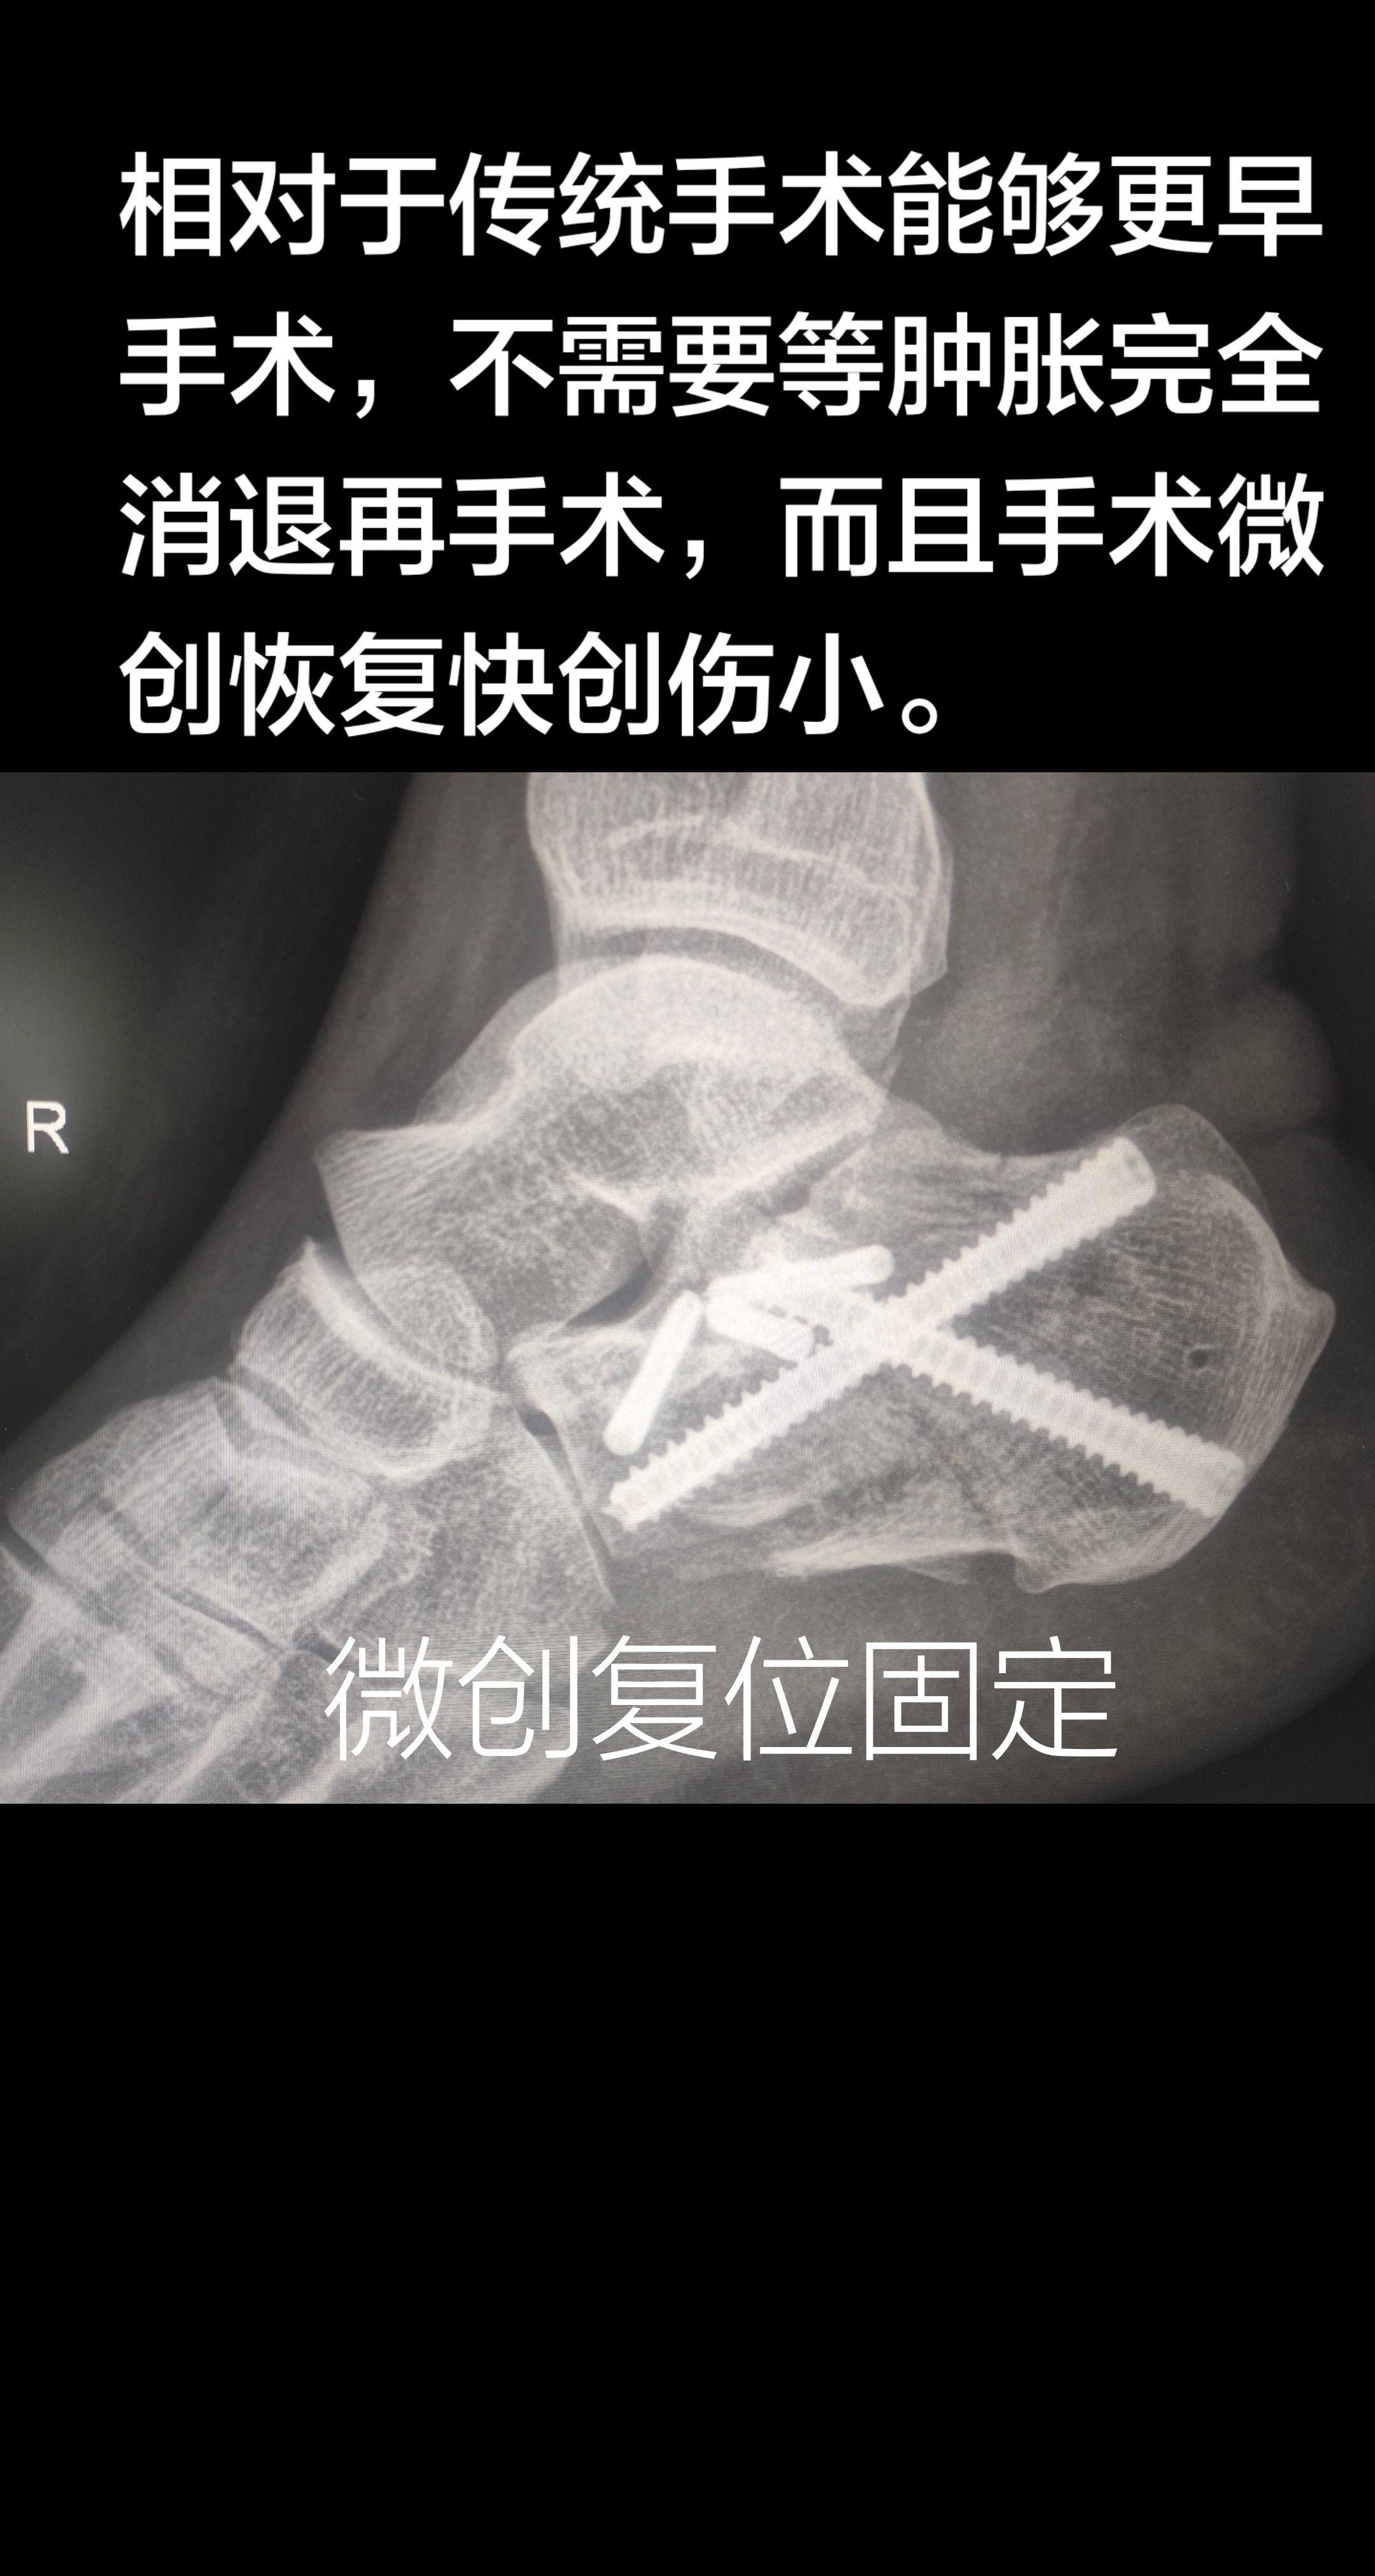

跟骨骨折。